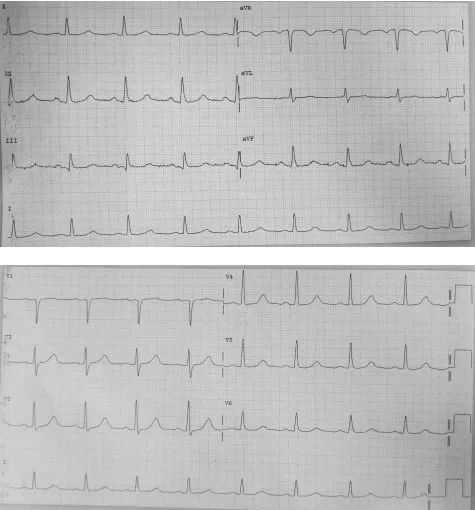

患者为56岁男性 , 既往有高血压病史4年 , 服用贝那普利、氢氯噻嗪治疗 , 自诉血压控制良好 , 体检时心电图如图1 。 患者有心室肥厚吗?

图1 心室肥厚?

心电图显示规则的心律 , 心率66次/分 , 每一个QRS波前都有P波 , PR间期恒定为0.20s , P波在I、II、aVF、V4-V6导联上为正向 , 为窦性心律 。 QRS时限为0.08s , 电轴正常 , 然而振幅增高 , V5导联R波为28mm , V2导联S波深度为22mm , 符合左心室肥厚的诊断标准(SV2+RV5≥35mm) 。 QT/QTc间期为380/400ms , V1-V3导联可见U波 。 综上所述 , 初步诊断为左心室肥厚 , 考虑与患者长期高血压相关 。

图1中的标准电压高度为20mm , 即双倍标准化电压(1mV=20mm) , 因此所有波形的电压都要压缩一半 , 调整为正常电压后复查心电图(图5) , V2导联S波振幅为1.1mV , V5导联的R波振幅为1.4mV , 心室肥厚诊断不成立 。 心电图正常 。